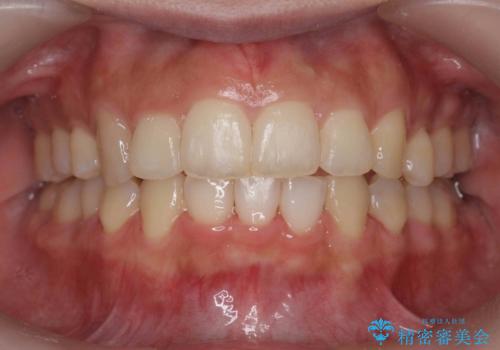

下顎がとても小さく後方位であるため、オトガイの閉口時のシワは完全になくすことは難しかったですが、前歯も大きく下がり満足していただきました。

矯正治療は審美的な側面を持っておりますが、小さすぎる下の顎に口元を無理やりあわせるのも、歯の移動量が大きすぎて適切な治療とは言えないと思います。健康を損なう美容整形とは違うからです。前歯については、適度に下げる量をコントロールすることも大事です。